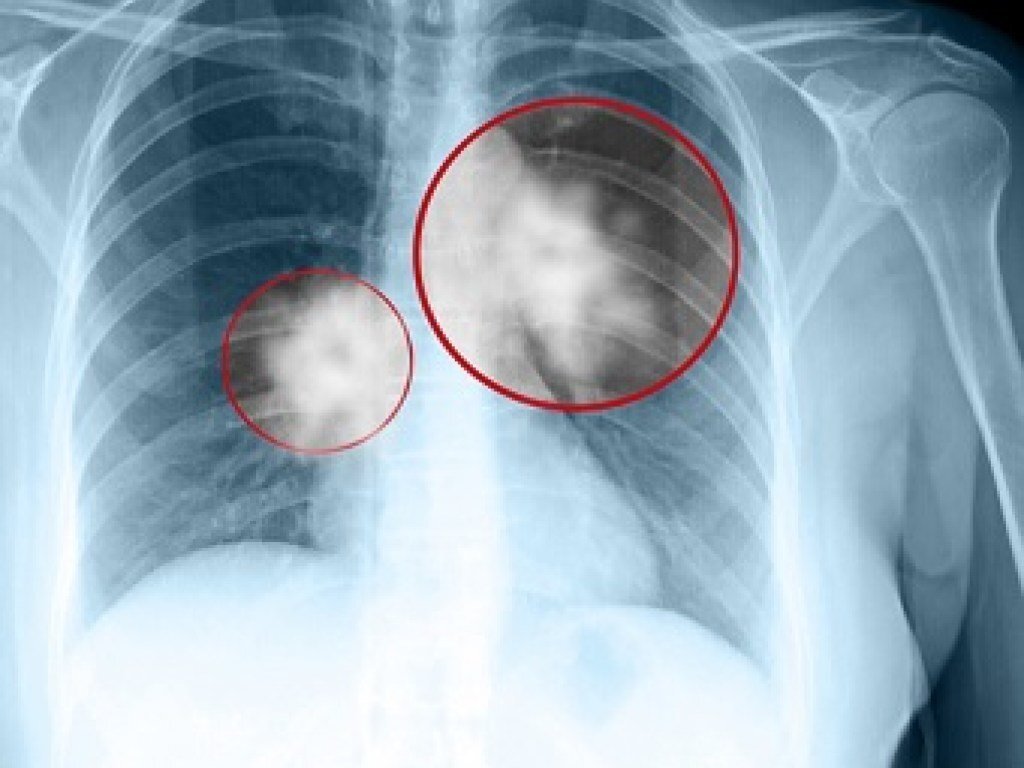

Рак легких – генетическая диагностика. Кому нужно ее проводить?

Опухолевые маркеры рака легкого представляют собой вещества, продуцируемые опухолевыми клетками. Нормальные клетки могут превращаться в опухолевые клетки вследствие генетической мутации, изменения нормальной функции генов. Некоторые генетические мутации могут быть унаследованы, другие приобретаются в процессе жизни из-за факторов окружающей среды или образа жизни. Мутации, вызывающие рак легких, обусловлены приобретенными, также известными как соматические, мутациями. Эти мутации чаще всего вызваны курением табака. Не все виды рака легких вызваны генетическими мутациями. Но если рак вызван мутацией, возможно проведение специфической терапии. Маркеры рака легких могут быть проверены индивидуально или сгруппированы вместе в одном тесте. Генетическая диагностика показана при немелкоклеточном раке легких (в частности: аденокарцинома легкого, крупноклеточный рак, плоскоклеточный и аденоплоскоклеточный рак и др.). Этот тип рака, скорее всего, будет иметь генетическую мутацию, которая будет р